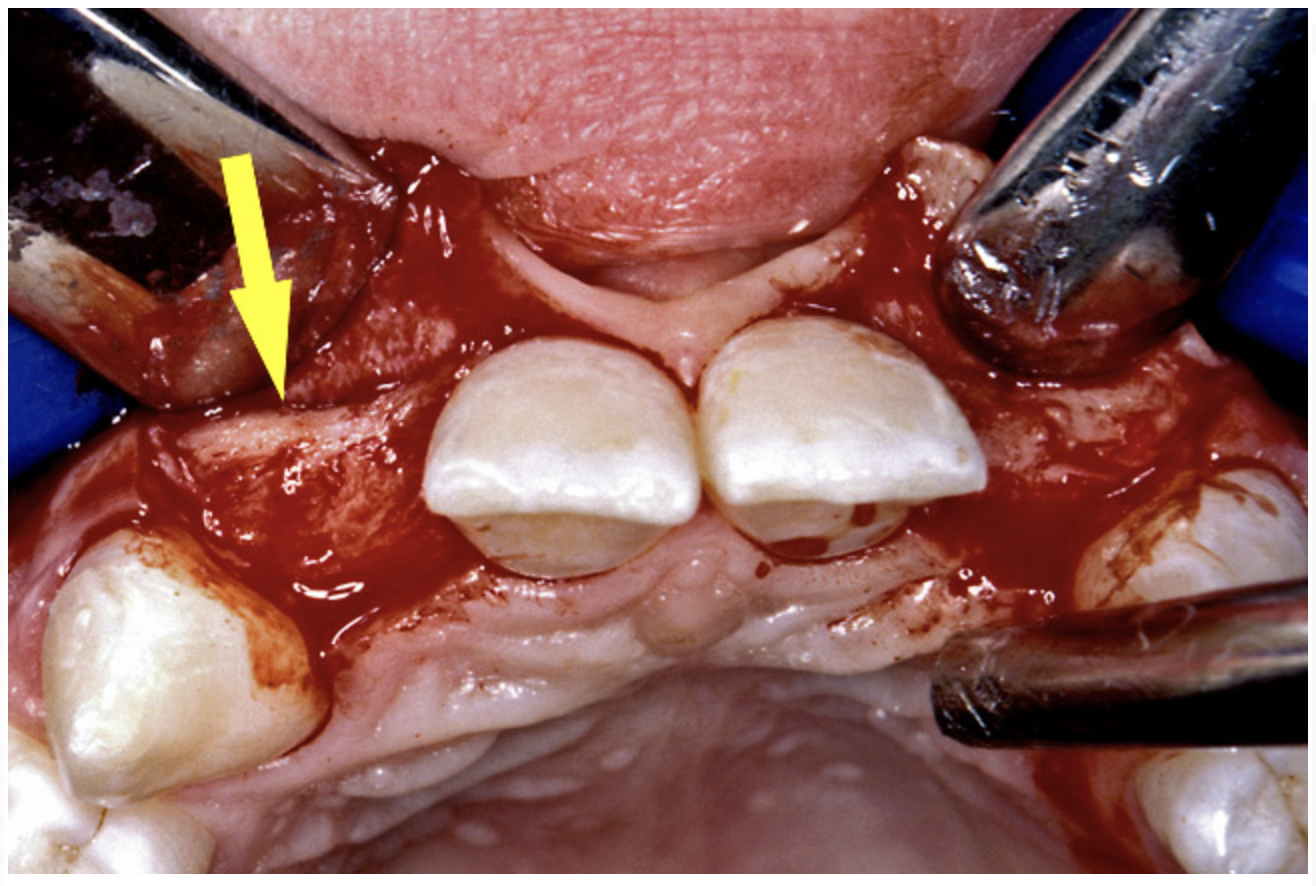

Before the day of surgery, the patient was seen by the orthodontist for the removal of the orthodontic brackets. The patient still was not pleased with the position of the two centrals, and it was determined that this would be addressed after implant placement (Figure 13A). The anatomical variations of the crestal tissue and lack of interdental papilla can be appreciated in the close-up views of the right and left sites (Figure 13B and 13C). There were no surprises on the day of surgery as all of the decisions were made during the planning phase, before the scalpel ever touched the patient. The occlusal view of the CT 3D model revealed the wider alveolar ridge on the right side and thinner crest on the left side (Figure 14A). This was confirmed when the full thickness mucoperiosteal flaps were elevated, and the underyling bone revealed (Figure 14B). The tooth-borne templates were designed to facilitate the drills and drilling sequence specific to the diameters of the predetermined implants (Figure 15A). Each template contained an embedded 5-mm long stainless steel tube, which was approximately 0.2-mm wider than each drill (just wide enough to allow for the drills to rotate freely). Once positioned over the natural teeth, the template was secure and offered precision accuracy in transferring the implant locations from the original software-designed plan, allowing the potential for internal and external irrigation (Figure 15B).

Figure 14a  The information gained from (A) the 3D model was confirmed when (B) the flaps were elevated.

Figure 14a

Figure 14b  The information gained from (A) the 3D model was confirmed when (B) the flaps were elevated.

Figure 14b